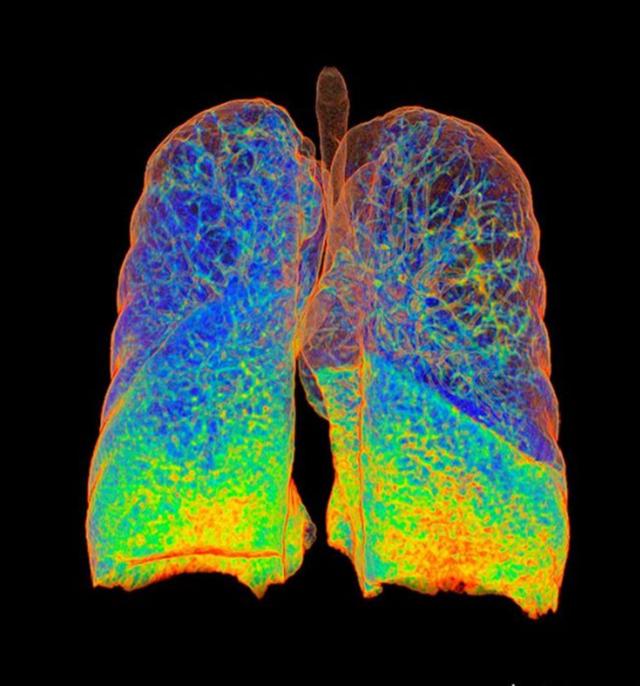

吸烟容易导致肺气肿,在X射线下它是这样的。